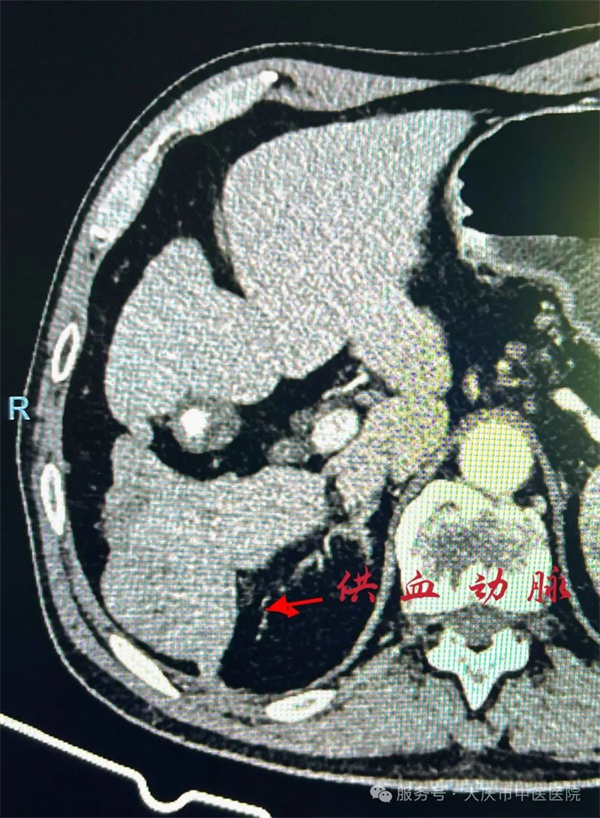

院微创介入团队结合检查结果术前充分评估,考虑患者由于多次介入后,肿瘤血供已经发生异位供血(右侧肾动脉供血)。再次通过微创介入精准施治,历时两个半小时,在局麻下为患者进行了精细TACE术。术后行C臂CT验证,肿瘤栓塞精准,无并发症发生。